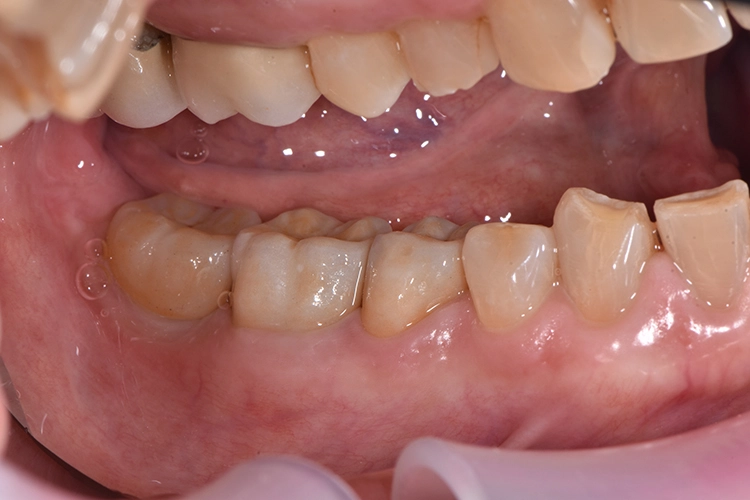

Bilder: Dr. Lampson / HannkerDie Kronen für die Zähne 45 und 46 wurden mit einem selbstadhäsiven Befestigungs-Composite (G-CEM LinkAce; GC*) auf den Pfeilerzähnen angebracht, die Krone für Zahn 47 auf das Implantat geschraubt (35 Ncm) und der Zugang im unteren Bereich mit Teflon, im oberen mit Composite gefüllt (Abb. 19). Nach Überprüfung der Okklusion wurde der Patientin das Endergebnis präsentiert.

Die CAD/CAM-Restaurationen aus Lithium-Disilikat fügten sich nahtlos in die natürliche Zahnreihe ein und wiesen perfekte, passgenaue Ränder auf. Die Patientin war mit dem natürlichen Behandlungsergebnis sehr zufrieden. Auch bei der Kontrolluntersuchung nach 2 Jahren, berichtete die Patientin nicht Negatives und befand die Kronen in Bezug auf Ästhetik und Funktion weiterhin als gelungen.